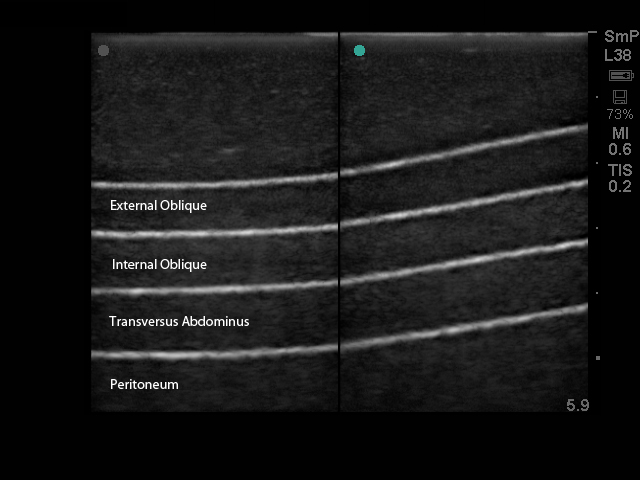

本模型能够与任何带腹部探头的超声影像检查设备连接使用,可用于培养用户关于超声引导下实施腹横肌平面(TAP)阻断局部麻醉手术相关的技能;当训练者练习穿刺腹外斜肌、腹内斜肌、腹横肌、和腹膜组织层时,可感受到真实的触觉感受。